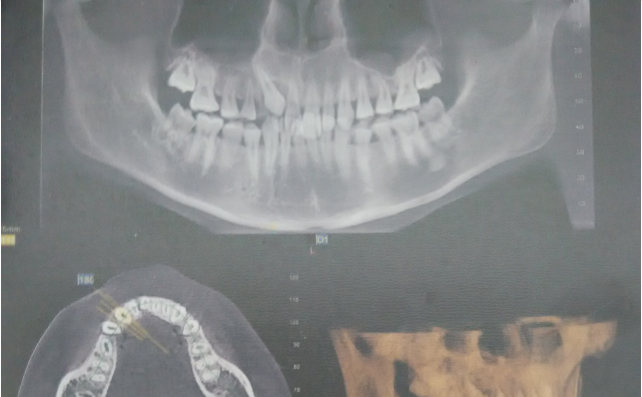

圖6.術(shù)前CBCT影像檢查:13位于腭側(cè)。準確定位,為下一步切除牙齦組織打好基礎(chǔ)。